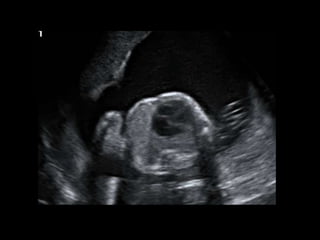

HISTORY

โ€ข 36 yo female 30.5 weeks pregnant

โ€ข Referred with โ€žmultiple fetal anomaliesโ€Ÿ for

fetal ultrasound